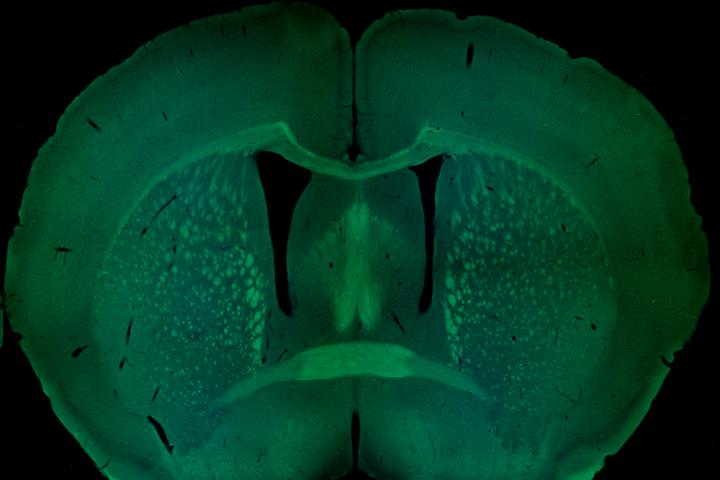

image: Coronal section of a mouse brain, with several major axonal tracts stained in green. Image courtesy of Dr. Ahlem Assali.